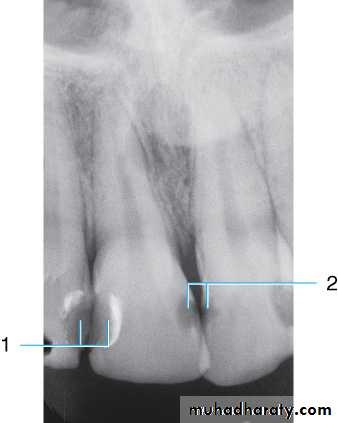

This radiograph shows (1) radiolucent restorations (composites) on the mesial surface of the lateral incisor and distal surface of the central incisor. Note that under both restorations is a base of radiopaque material. (2) The radiolucencies on the mesial surfaces of both central incisors are carious lesions.

Restorative Materials & Decay

Retention pins. (1) Radiopaque pins help retain the radiolucent composite restorations. (2) Small radiopaque amalgam restorations.